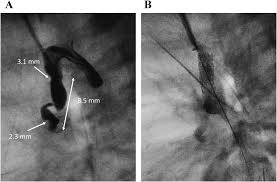

日本小児循環器学会雑誌